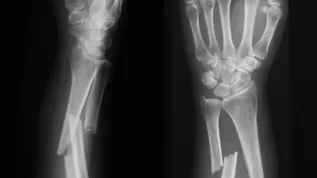

The authors of the invention point out that the number of cases of osteomyelitis has tripled in the last 40 years. At the same time, they explain, necrotic changes resulting from bone infection can be seen in an X-ray examination only after 50-75 percent of the bone matrix is destroyed.